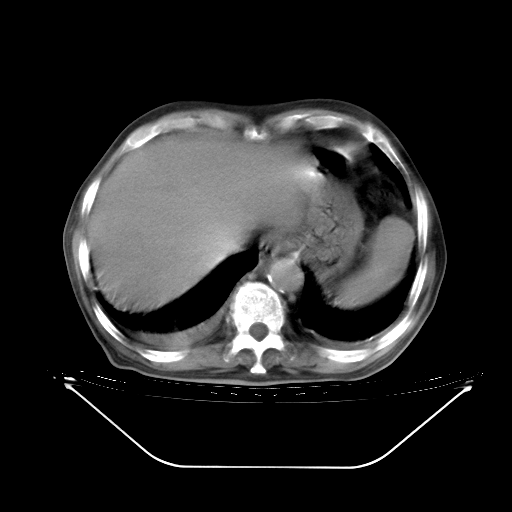

今天复查肺部CT,发现双肺广泛磨玻璃样改变。所以我把3月19日和5月9日相隔50天的肺部CT上传。请大家会诊。

5月9日肺部CT(在4月27日齐鲁医院肺部CT描述部分肺组织磨玻璃样改变,12天后肺组织广泛磨玻璃样改变)

2009年5月9日肺部CT

大致读了系列胸部CT:纵隔窗无明显异常,肺窗:从4、27至今:主要是双肺中下野外带可见毛玻璃样改变,目前处于急性肺泡炎阶段,至于原因考虑1、结替组织或胶原血管性疾病所致?2、恶性疾病如恶组在肺部所致的表现或细支气管肺泡癌?3、药物或其它原因如肺蛋白沉着症所致肺泡炎目前不太可能?总之,明天就去请我院的呼吸科、感染科、血液科和临免专家会诊哈。